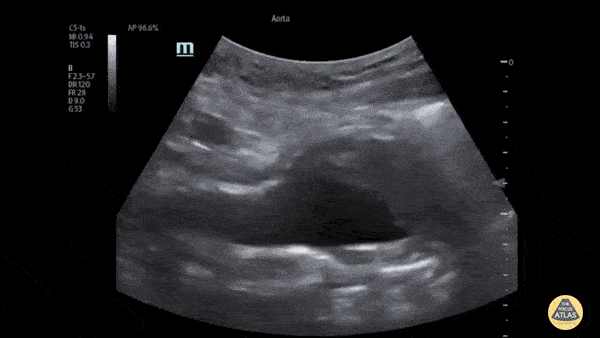

Aorta - AAA with Intramural Thrombus

The patient presented to the ED with a known abdominal aortic aneurysm (AAA). A point-of-care ultrasound (POCUS) examination of the abdominal aorta was performed using a curvilinear probe (longitudinal view shown). An infrarenal AAA was noted adjacent and superior to the bifurcation and measured a maximum diameter of approximately 5cm. Heterogeneous echogenic material was seen within the lumen of the aneurysm in keeping with intramural thrombosis, along with a hyperechoic line representing a chronic dissection. This demonstrates the utility of POCUS in the rapid diagnosis of AAA and evaluation of size and intraluminal features such as intramural thrombus and dissection. Andrew Namespetra, MB BCh BAO MSc PGY-1 Emergency Medicine Resident, Central Michigan University (CMU) Chad Bambrick, MD PGY-2 Emergency Medicine Resident, CMU Ryan Davis MS4, CMU College of Medicine